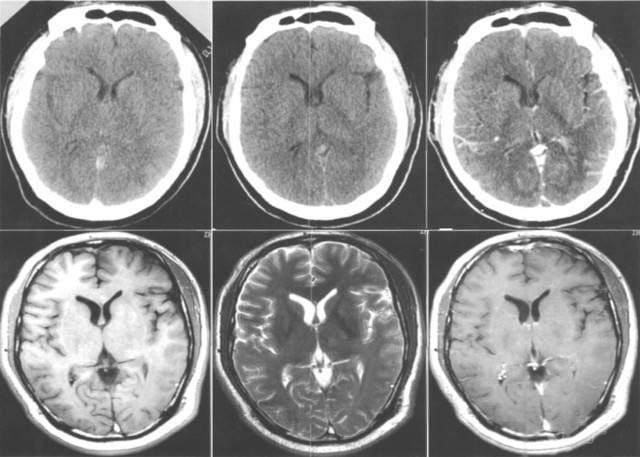

病例一

患者徐某某 ,女,55歲,家住濰坊市經(jīng)濟開發(fā)區(qū)馬家埠村?;颊弑患覍侔l(fā)現(xiàn)突然意識不清,呼之不應(yīng),惡心、嘔吐,右側(cè)肢體癱瘓。

家屬撥打120求救電話之后,由120救護車將患者接到市立醫(yī)院急診科。經(jīng)顱腦CT檢查后診斷為“腦出血”,主管醫(yī)師迅速對該患者進行了腦出血微創(chuàng)手術(shù),病情及時得以控制,病人轉(zhuǎn)危為安。手術(shù)12天后,病人能夠自行進食,獨立完成更衣、穿鞋等動作,自行走出病房并順利出院。事后,患者家屬送來錦旗表示感謝。